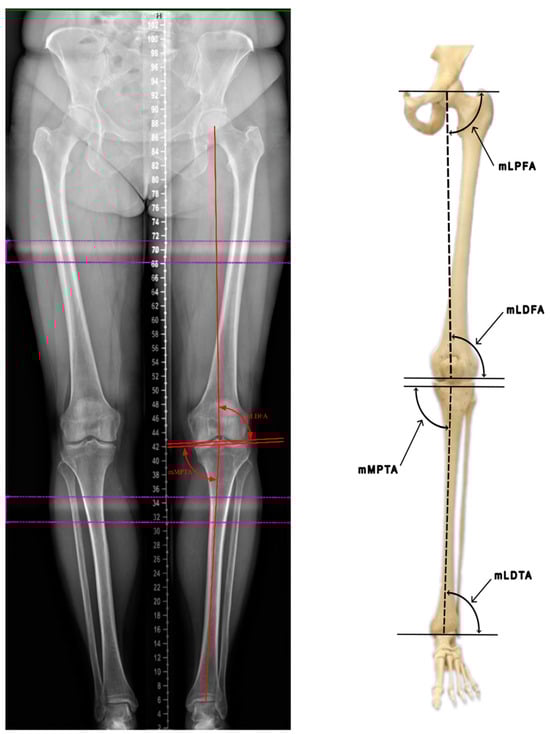

1.3. Evaluation of Lower-Limb Angles

The anatomical tibiofemoral angle (TFA), also known as the hip–knee–ankle angle (HKA), is measured between the anatomical axes of the femur and the tibia, with a normal range of 1–1.5° in healthy individuals. In order to accurately measure the TFA, a line corresponding to the anatomical axis of the femur should be extended to form an angle with the anatomical axis of the tibia. The mechanical axis of the femur forms a physiological angle of 6° ± 1° with the anatomical femoral axis, referred to as the anatomical–mechanical femoral angle (MFA) (Figure 2).

Specific angle measurements based on the mechanical axis of the lower-limb bones and their physiological ranges are shown in Table 1.

Abbreviations: mechanical lateral proximal femoral angle (mLPFA); mechanical lateral distal femoral angle (mLDFA); mechanical medial proximal tibial angle (mMPTA); mechanical lateral distal tibial angle (mLDTA).

Figure 2. Evaluation of lower-limb angles (based on Luís et al. [8]).